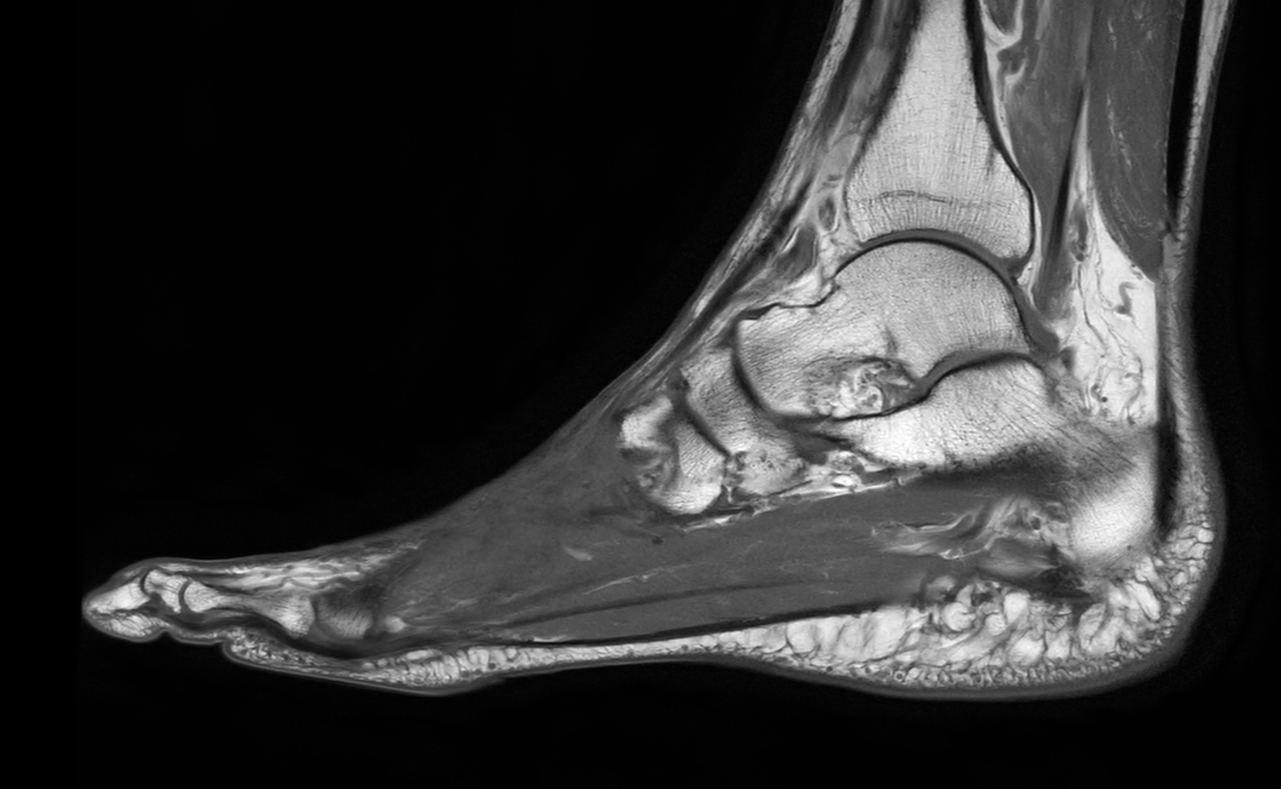

Ankle/Foot imaging post-amputation

Patient with partial amputation of the foot

Sagittal PDw mDIXON XD TSE (Water only)

Sagittal PDw mDIXON XD TSE (In Phase)

Sagittal PDw mDIXON XD TSE (Partial FatSat)

Sagittal T1w TSE

Sagittal T1w TSE with gado

Sagittal T1w TSE with gado (subtraction)